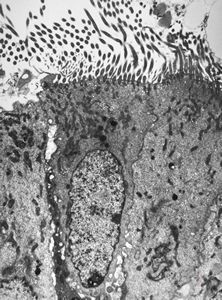

M,22y. | normal bronchial epithelium